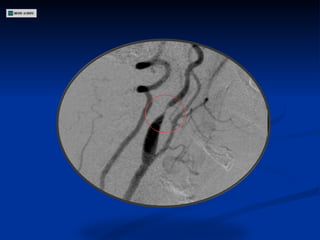

ECODOPPLER DE VASOS DEL CUELLO Estenosis 80-90 % en segmento inicial de Carótida Interna Derecha Estenosis 50-60 % en Carótida Interna Izquierda Carótidas externas permeables con flujos conservados Arterias Vertebrales permeables

Angiografía

ECODOPPLER DE VASOSDEL CUELLO Estenosis 80-90 % en segmento inicial de Carótida Interna Derecha Estenosis 50-60 % en Carótida Interna Izquierda Carótidas externas permeables con flujos conservados Arterias Vertebrales permeables